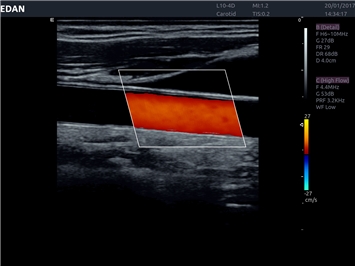

EDAN Acclarix LX4 представляет собой инновационную ультразвуковую систему, построенную на усовершенствованной платформе Acclarix. Сочетание высокого качества визуализации с интеллектуальным рабочим процессом делает эту систему оптимальным выбором для клиник, ценящих эффективность и экономичность.

• Сосудистой диагностики

Цветовой допплер:

Недопплеровская визуализация кровотока:

Направленный энергетический допплер: